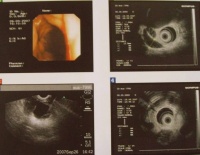

胆管癌超声内镜检查

2.B超检查:反复仔细的B超检查可显示扩张的胆管梗阻的部位甚至肿瘤胆管癌的超声像可呈肿块型条索状突起型及血栓状肝内胆管癌常呈肿块或条索状肝门部癌常为条索状下部胆管癌常为突起型肝门部血栓状声像可能是肝门癌胆囊癌或转移癌由于胆管扩张发生在黄疸之前B超具有诊断早期胆管癌的价值